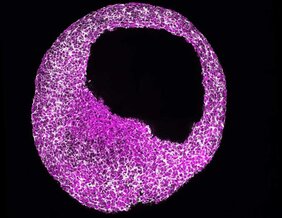

Um das Regulationsprogramm hinter der Herzentwicklung zu verstehen, verwendete die Arbeitsgruppe Modelle auf der Basis embryonaler Stammzellen, die die Entscheidungen über das Schicksal des menschlichen Herzens in Zellkultur unter chemisch definierten Bedingungen widerspiegelt. Die Verwendung von aus menschlichen Stammzellen abgeleiteten Modellen ermöglicht es dem Team, humanspezifische Eigenschaften zu identifizieren, die sich drastisch von denen anderer Tiere unterscheiden können. Das Ziel dieses Ansatzes ist es, mit den präzisesten Modellen zu arbeiten, die der menschlichen Biologie am nächsten kommen. Auch Tierversuche können so minimiert werden.

Das Team fand heraus, dass die Kompetenz für das zukünftige Schicksal des Herzens in menschlichen embryonalen Stammzellen (hESCs) durch einen spezialisierten mRNA-Translationskreislauf voreingestellt wird, der durch das RNA-bindende Protein RBPMS gesteuert wird. RBPMS wird in hESCs zu aktiven Ribosomen rekrutiert, der molekularen Maschine, die Proteine aus mRNA herstellt. Dort kontrolliert RBPMS die Produktion wesentlicher Faktoren, die für das Programm benötigt werden, das die Stammzellen dazu bringt, sich zu Herzzellen zu entwickeln.

Es wird angenommen, dass die Fähigkeit der Stammzellen, sich zu künftigen Herzlinien zu entwickeln, durch den frühen Kontakt mit kardiogenen Signalen vorbestimmt wird. Die Studie zeigt, dass der RBPMS-vermittelte selektive mRNA-Translationskreislauf die zelluläre Fülle der „Morphogen-Signalinfrastruktur“ genehmigt, die für die Zulassung des Herzmesoderms in hESCs erforderlich ist. Somit stellt RBPMS die zukünftige kardiale Kompetenz von hESCs durch die Programmierung selektiver mRNA-Translation her.